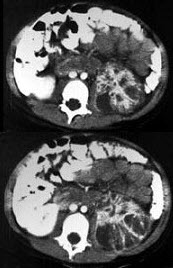

男,5岁,有尿路感染伴急性发热,CT增强扫描如图所示,最可能的诊断是( )

A、左侧肾炎

B、左侧肾脓肿

C、左侧急性肾盂肾炎

D、左侧黄色肉芽肿性肾盂肾炎

E、左侧慢性肾盂肾炎

点击查看答案